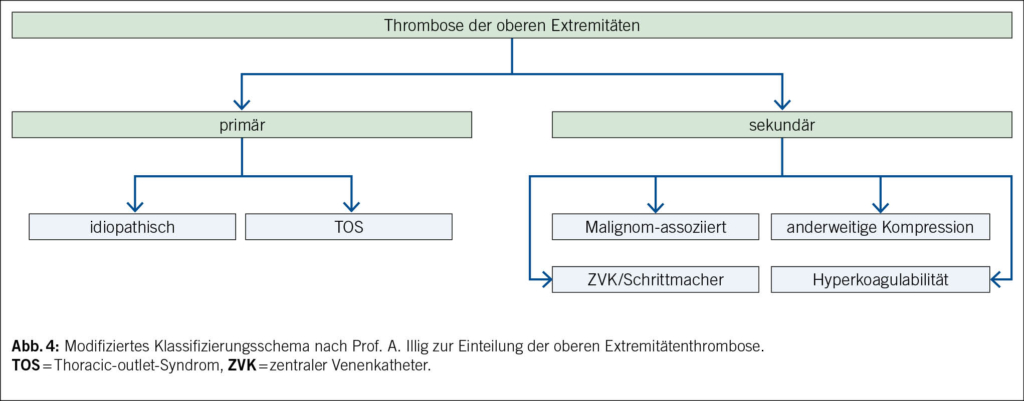

In der Literatur werden Thrombosen der Vena jugularis sowie Armthrombosen (V. subclavia, V. axillaris, V. brachialis) in primäre und sekundäre Thrombosen unterteilt, wobei diese Einteilung international nicht einheitlich definiert ist (4). Primäre Thrombosen der oberen Extremitäten entstehen entweder im Rahmen eines Thoracic-outlet-Syndroms (TOS) oder idiopathisch. Bei unserem Fall waren weder anamnestische noch radiologische Hinweise auf ein TOS zu finden. Nach aktuellen Studien wird bei etwa 25 % der Patienten mit idiopathischer Thrombose innerhalb eines Jahres eine maligne Neoplasie diagnostiziert, und bei 25–42 % wurde eine Hyperkoagulabilität festgestellt (5). Diese Zahlen unterstreichen die Notwendigkeit einer gründlichen Ursachensuche bei der Diagnostik von atypischen Thrombosen, insbesondere auch einer Thrombophilieabklärung (Tab. 1) (6).

Sekundäre Thrombosen entstehen in der Regel im Rahmen klar definierter Ursachen wie der Platzierung von zentralvenösen Kathetern oder Herzschrittmachern, vorbestehenden malignen Erkrankungen, einer Hyperkoagulabilität oder nach Trauma im Bereich des Halses oder Oberarms. Thrombosen der V. jugularis interna können auch im Zusammenhang mit dem Lemierre-Syndrom auftreten. Obwohl beim vorliegenden Patienten zu einem späteren Zeitpunkt ein malignes Tumorleiden diagnostiziert wurde, bleibt die Ätiologie der Thrombose nicht abschliessend geklärt. Da es sich beim gefundenen Urothelkarzinom um ein lokal begrenztes, nicht muskelinvasives Karzinom handelt, ist eine systemische Thrombosierung als Tumorkomplikation gemäss der Literatur unwahrscheinlich (Abb. 4).